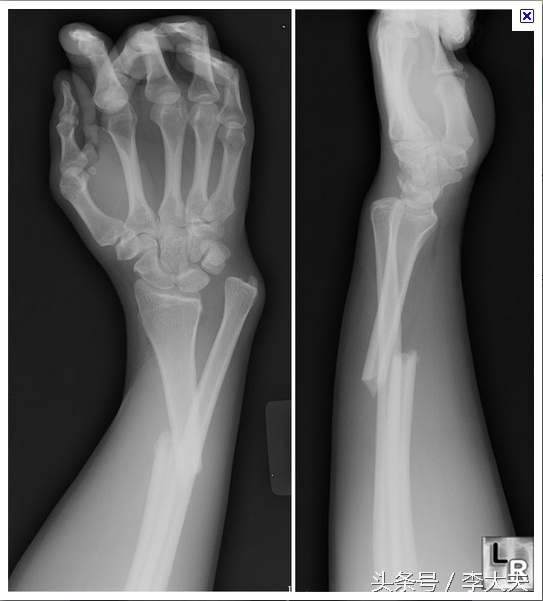

上肢双骨折X线片